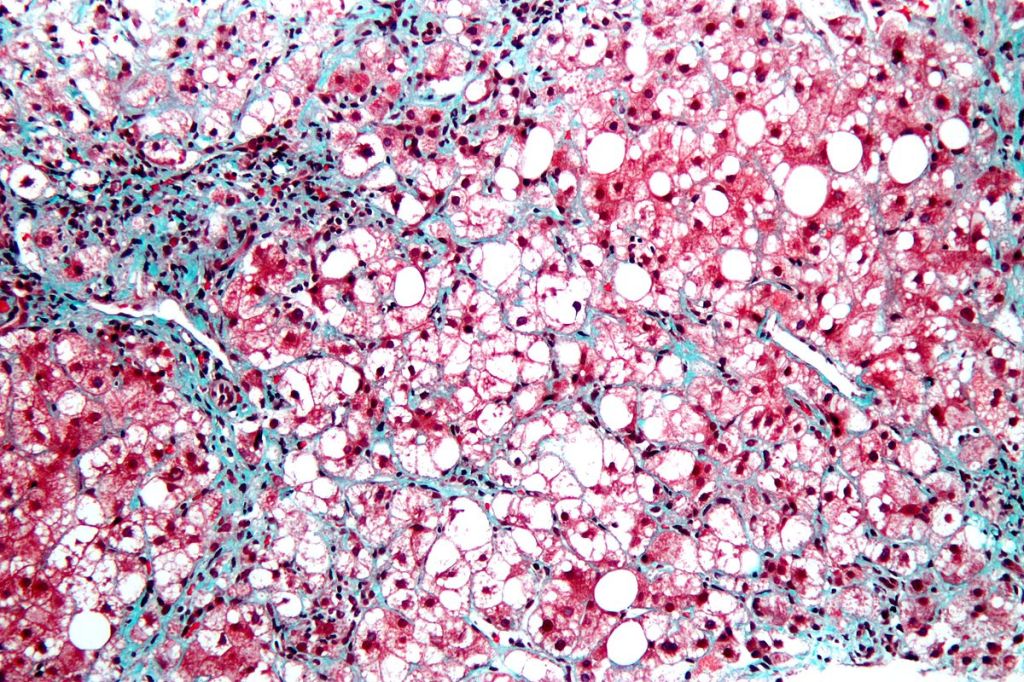

NAFLD, more commonly known as nonalcoholic fatty liver disease, is one of the most prominent chronic liver conditions in the country and is characterized by the accumulation of fat in hepatocytes (liver cells). A cousin of NAFLD, nonalcoholic steatohepatitis (NASH), is a condition that both encompasses the deposition of fat in the liver and inflammation of the organ. Fibroblast growth factor 21 (FGF21), which is naturally elevated by high-fat diets, has been found to reverse steatohepatitis in obese mice and reduce the risk of insulin sensitivity. However, a widely-used antiseptic called Triclosan (TCS) has been shown to promote elevated liver fat levels due to oxidative stress in species such as tadpoles and seemingly diminish the function of FGF21. Researchers at the Department of Pharmacology at the University of California, San Diego sought to find a more solid connection between high-fat diets (HFDs) and TCS toxicology.

Researchers began by grouping 4-week old mice in 2 separate groups where the control was fed an HFD consisting of 59% fat, 15% protein, and 26% carbohydrates dissolved in 0.2% dimethyl sulfoxide (DMSO). The experimental group was given the same chow-fed diet along with 0.35 mM of TCS dissolved in 0.2 % DMSO as well. After a 4 to 4.5 month period, the mice’s livers were harvested for gene analysis under histological parameters. After the 18 week testing period, the mice fed with an HFD showed elevated levels of circulating FGF21 compared to the experimental group. This confirmed previous studies with the conclusion that FGF21 displayed an adaptive response in preventing lipid accumulation and improving insulin stability. The group treated with TCS, however, saw lower levels of FGF21 in the mice livers. This proves that exposure to TCS disrupted the regulation of FGF21 normally stimulated by high-fat diets, thus making subjects under HFDs more susceptible to liver diseases.